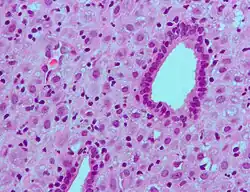

ESCs are the connective tissue cells of the endometrium that are fibroblastic in appearance. However, decidualization causes them to swell up and adopt an epithelial cell-like appearance due to the accumulation of glycogen and lipid droplets. Furthermore, they begin secreting cytokines, growth factors, and proteins like IGFBP1 and prolactin, along with extracellular matrix (ECM) proteins such as fibronectin and laminin. The increased production of these ECM proteins turns the endometrium into the dense structure known as the decidua, which produces factors that promote trophoblast attachment and inhibit overly aggressive invasion.[7]

The decidual reaction is seen in very early pregnancy in the generalized area where the blastocyst contacts the endometrial decidua. It consists of an increase in secretory functions of the endometrium at the area of implantation, as well as a surrounding stroma that becomes edematous.[8]